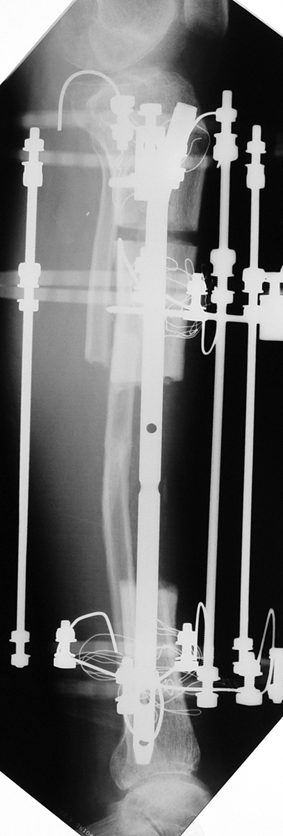

Appropriate radical debridement necessitates excision of all necrotic bone and soft tissues, and frequently causes instability at the involved extremity. The remaining bone and soft tissue defect has to be fixed and reconstructed. The distraction osteogenesis method of Ilizarov is used successfully for achievement of union, correction of the deformity, elimination of limb length inequality and reconstruction of segmental bone defects.

The duration of external fixation (external fixation index) depends on the amount of distraction required, and the extremity is prone to complications during this period. After the distraction phase is completed, the external fixator remains in place during the consolidation phase, which lasts twice as long as the distraction phase; but this period is hardly tolerated. If the external fixator is removed before sufficient consolidation is achieved, fractures, deformity and shortness will be the result. In our department, ‘lenghthening over nail’ method is used in order to decrease the external fixation index and increase patient comfort and activity level. In this method, the intramedullary nail is statically locked after the completion of the distraction phase, and external fixator is removed. The extremity is stabilized by the intramedullary nail during consolidation phase. In this way, complications due to long external fixation index or early removal of the external fixator are avoided.